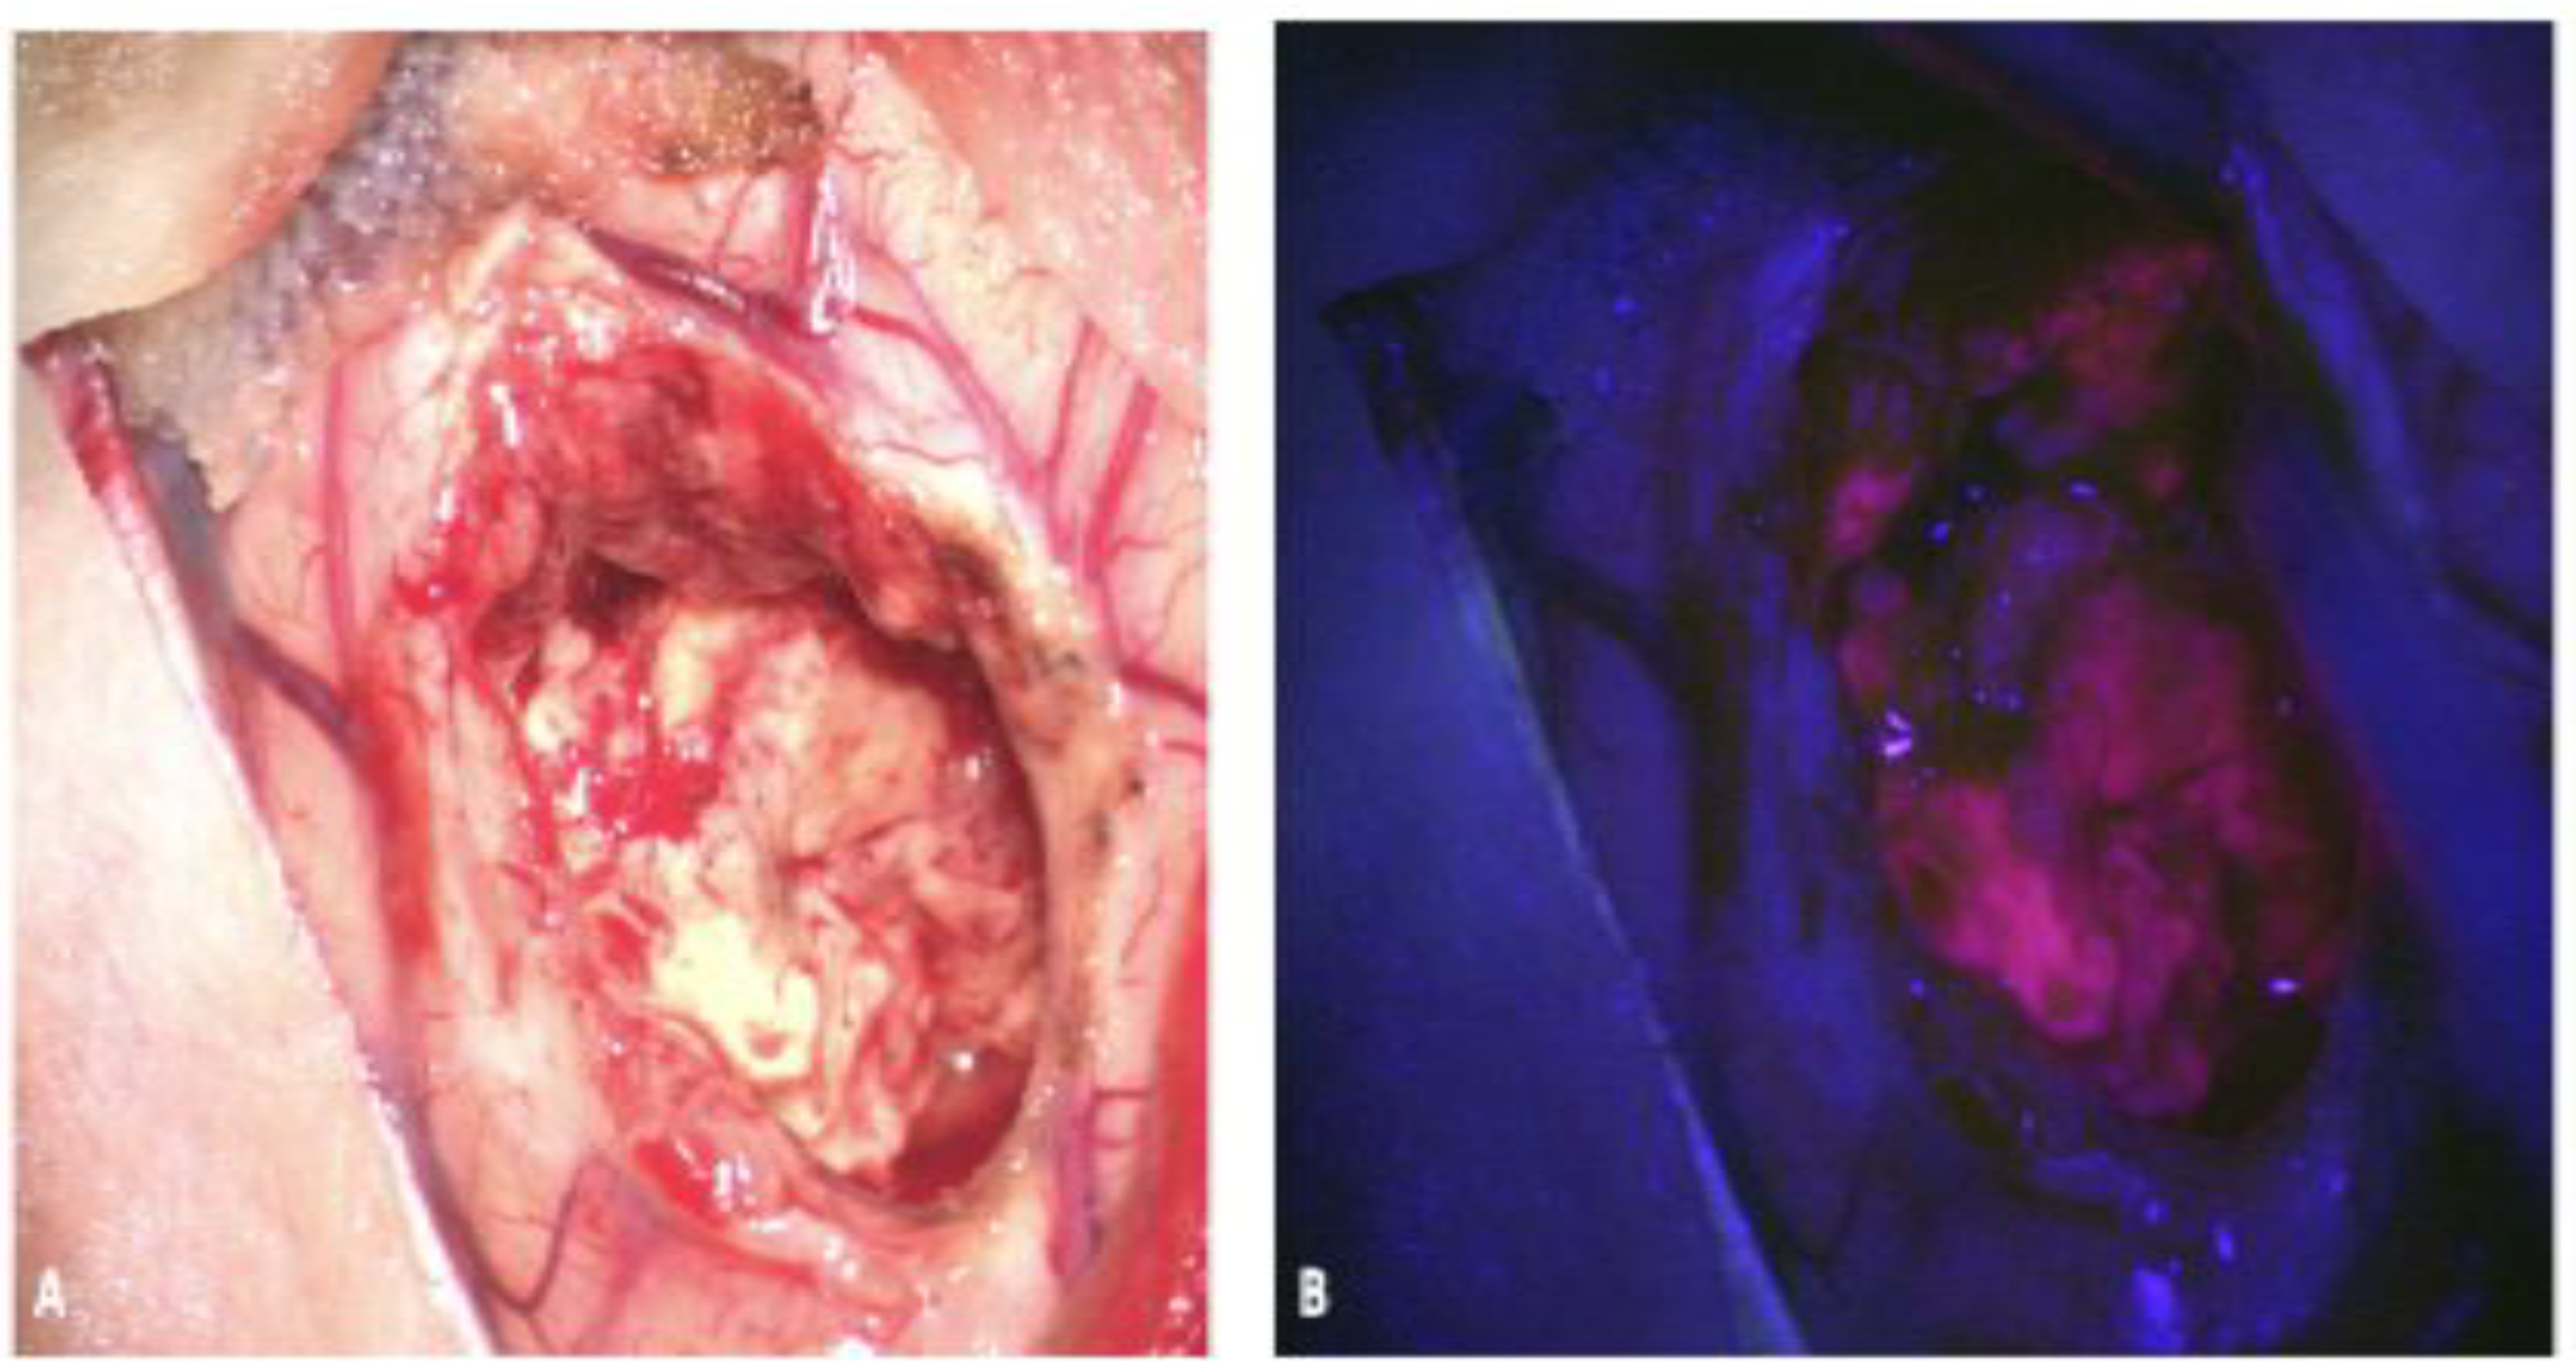

2.1. 5-Aminolevulinic Acid (5-ALA)

2.1.1. 5-ALA: Background and Mechanism of Action

2.1.2. 5-ALA: Limitations

2.1.3. 5-ALA: Evidence for Use